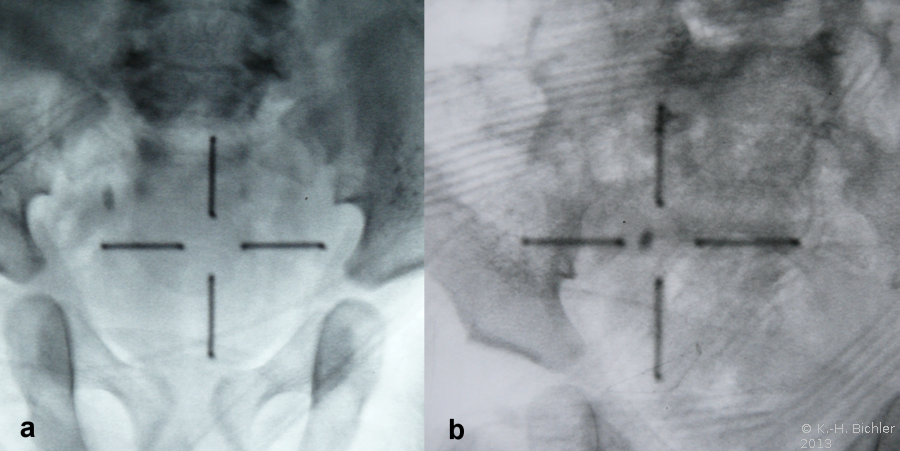

Bei dem 1 Jahre alten Mädchen fand sich bei rezidivierendem Harnwegsinfekt mit pyelonephritischen Veränderungen links und vesikoureteraler Reflux beiderseits ein Nierenbeckenstein links (

Abbildung 5abc). Im Infektfreien Intervall erfolgte die Stoßwellenbehandlung (